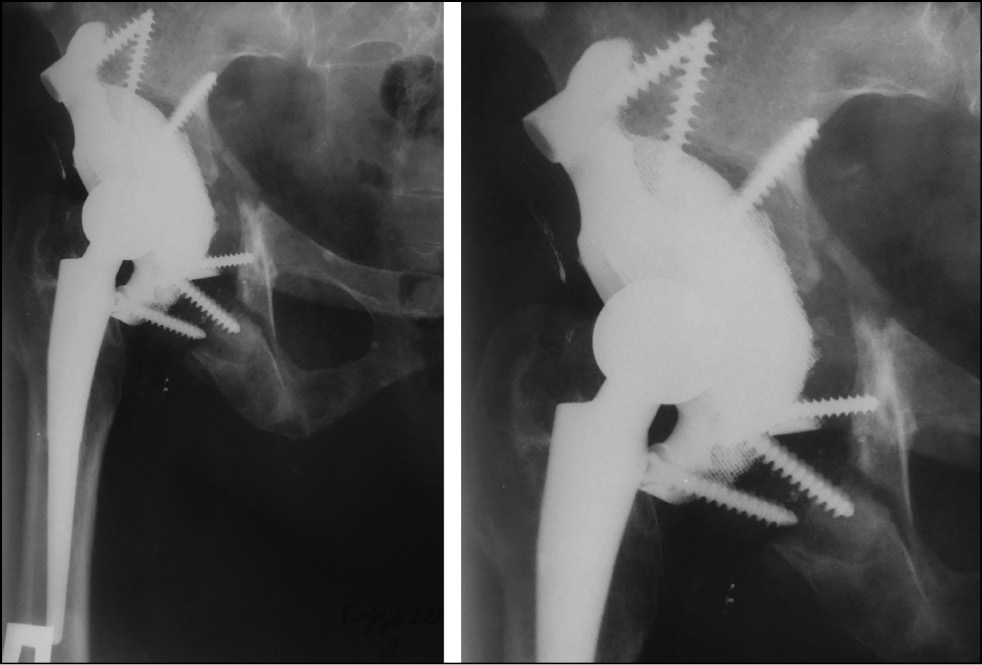

For a more detailed visualization of the defect of the bones forming the acetabulum, multispiral computed tomography (CT) with 3D reconstruction was performed (Fig. 2).

Fig. 2. 3D reconstruction of the right acetabulum by imaging using multislice computed tomography.

Given the severity of the acetabular defect and the extreme difficulty of reconstruction using standard components, a customized acetabular component was used. In collaboration with “Endoprint” engineers, a 3D model of the implant was created in accordance with the bony defect of the acetabulum (Fig. 3).